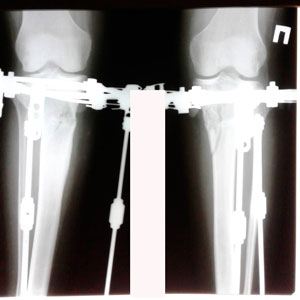

Исходник 32 года. Якутия

Дата операции - 05.02.2020г